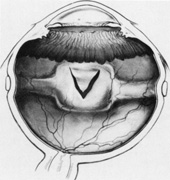

One result of circumferential encircling scleral buckles is fish-mouthing of retinal breaks.72,73 This is caused by the relative circumferential shortening of the sclera and choroid induced by the buckle in relation to the retina. This relative excess of retinal surface causes the retina to lie in radial folds over the buckle. These folds, in conjunction with vitreous traction, can result in the failure of retinal breaks to settle over the buckle. The breaks may form an elongated oval configuration in the anteroposterior meridian over the buckle, resembling the open mouth of a fish (Fig. 23). Persistent elevation of the retina resulting from the fishmouth phenomenon can result in surgical failure and therefore needs to be addressed.

Fig. 23. Fishmouth appearance after circumferential buckle.